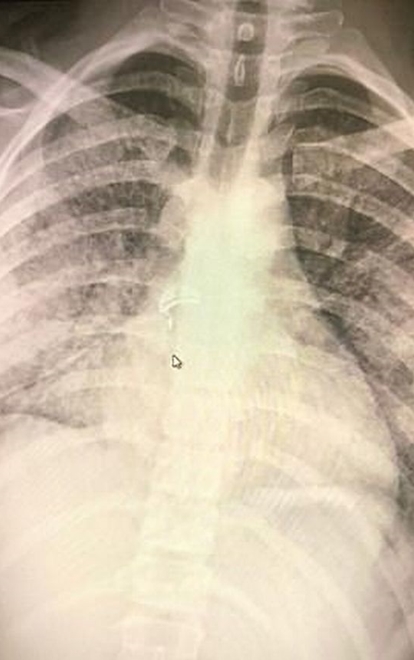

Phổi của Adam Hergenreder giờ không khác lá phổi của một người 70 tuổi. Ảnh: Mirror